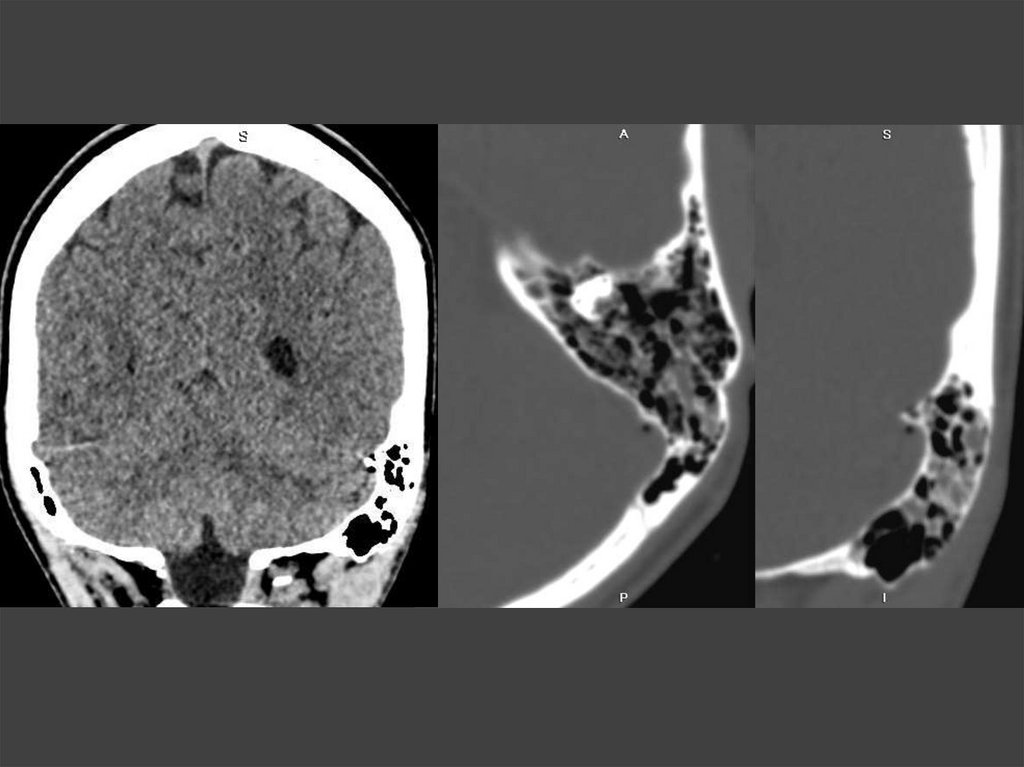

74. Остеома височной кости